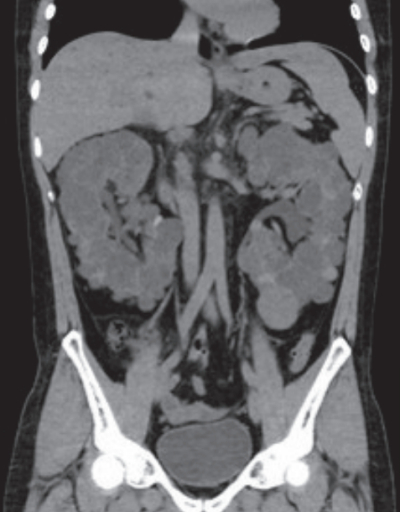

尿所見:蛋白(-)、糖(-)、潜血(-)。血液所見:赤血球 444 万、Hb 12.7 g/dL、Ht 39 %、白血球 4,900、血小板 21 万。血液生化学所見:総蛋白 7.3 g/dL、アルブミン 4.8 g/dL、尿素窒素 19 mg/dL、クレアチニン 1.9 mg/dL、尿酸 6.6 mg/dL、Na 142 mEq/L、K 4.5 mEq/L、Cl 107 mEq/L、Ca 9.1 mg/dL。腹部単純 CT 冠状断像を別に示す。